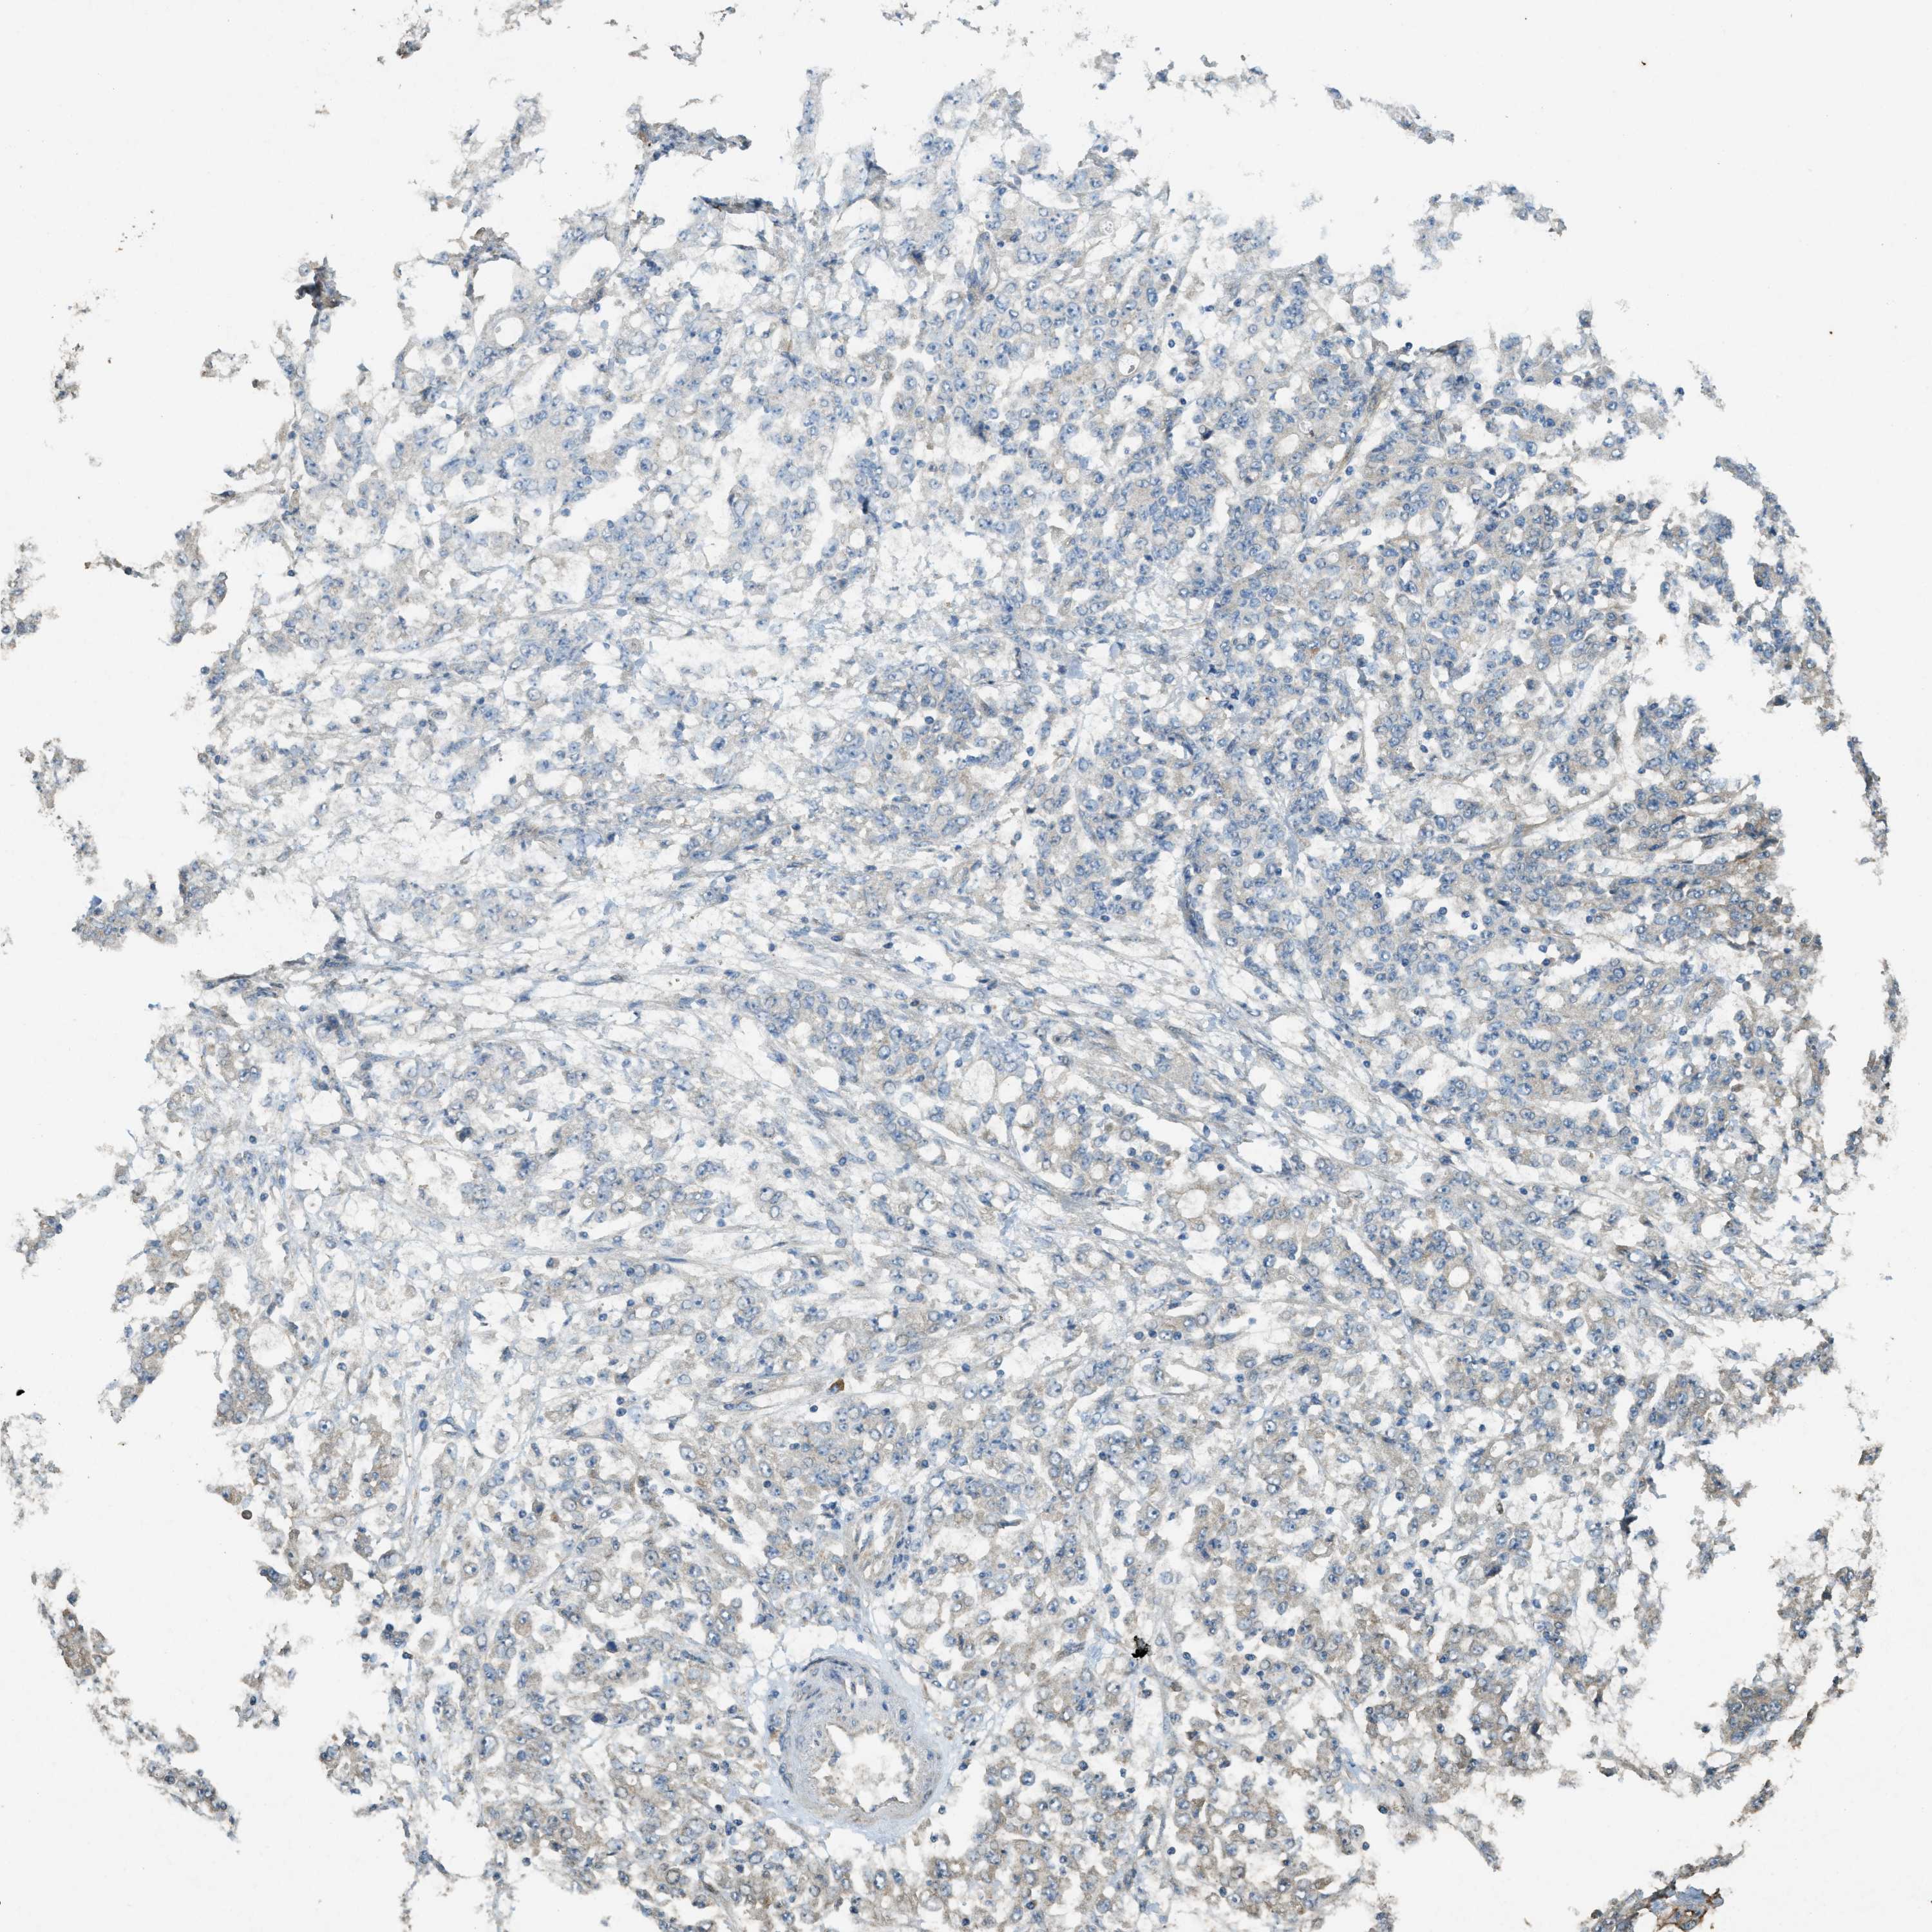

STOMACH CANCER - Protein expressioni

A mouse-over function shows sample information and annotation data. Click on an image to view it in a full screen mode. Samples can be filtered based on level of antibody staining by selecting one or several of the following categories: high, medium, low and not detected. The assay and annotation is described here.

Note that samples used for immunohistochemistry by the Human Protein Atlas do not correspond to samples in the TCGA dataset.

Antibody stainingi

Antibody staining in the annotated cell types in the current human tissue is reported as not detected, low, medium, or high, based on conventional immunohistochemistry profiling in selected tissues. This score is based on the combination of the staining intensity and fraction of stained cells.

Each image is clickable and will lead to virtual microscopy that enables deeper exploration of all samples and also displays staining intensity scores, fraction scores and subcellular localization as well as patient and tissue information for each sample.

Antibody HPA009285

Antibody HPA017139

Antibody CAB017826

Staining

High

Medium

Low

Not detected

Intensity

Strong

Moderate

Weak

Negative

Quantity

>75%

75%-25%

<25%

None

Location

Nuclear

Cytoplasmic/membranous

Cytoplasmic/membranous,nuclear

Adenocarcinoma, NOS

Adenocarcinoma, High grade